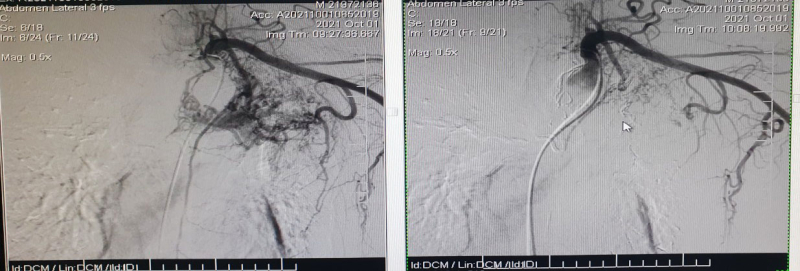

Hình ảnh nút động mạch phế quản trước (bên trái) và sau can thiệp (bên phải) trên màn hình DSA

Bệnh nhân được chỉ định can thiệp nút mạch xử trí tình trạng ho ra máu dưới hướng dẫn của hệ thống số hóa xóa nền DSA. Đánh giá về ca can thiệp, Bác sĩ Lê Tiến Hưng – Khoa Chẩn đoán hình ảnh, Bệnh viện Bãi Cháy cho biết: “Đây là ca tổn thương mạch máu rất phức tạp, có nhiều mạch máu ở các vị trí khác nhau cấp máu cho phế quản bị tổn thương (bao gồm động mạch phế quản trái, nhánh động mạch thuộc động mạch vú trong bên trái, nhánh động mạch thuộc thân giáp cổ bên trái, nhánh động mạch thuộc động mạch dưới vai trái). Chúng tôi đã xử trí nút mạch thành công các nhánh mạch tổn thương, kiểm soát được tình trạng ho ra máu cho người bệnh. Với kĩ thuật này, bệnh nhân chỉ cần gây tê tại chỗ, vẫn tỉnh táo trong quá trình can thiệp, phục hồi sức khỏe nhanh chóng chỉ sau 24 theo dõi”.